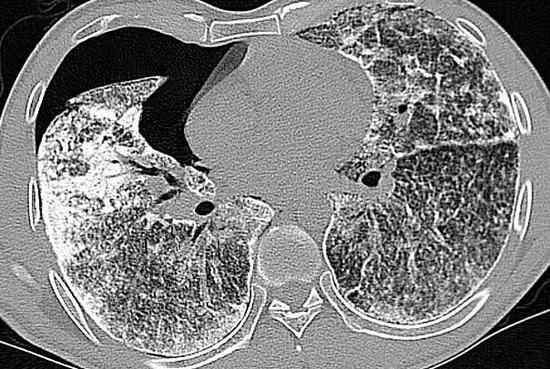

肺小结节影像诊断

听过肾结石,胆结石,咋还有肺结石?| chest病例_网易订阅

女病人哭诉活60岁,咳痰咳40年,专攻女性中肺的肺炎怎样形成的